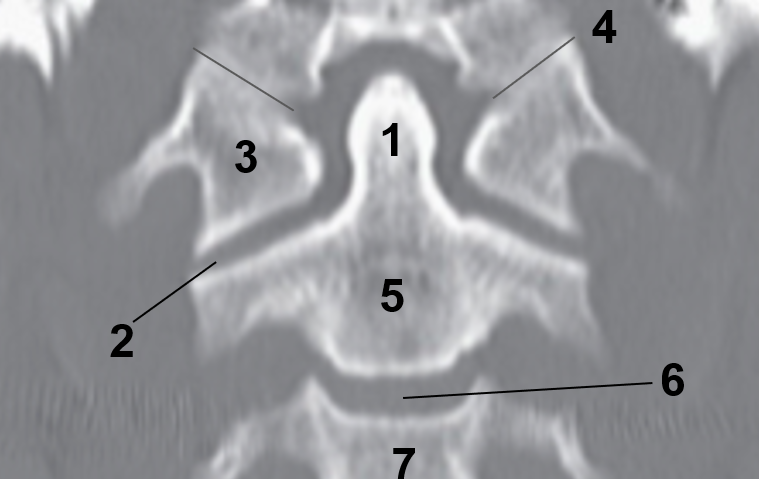

1?

Nasal Bone

2?

Maxillary Sinus

3?

External Acoustic Meatus

4?

Pons

5?

Cerebellum

6?

Mastoid Air Cells

7?

Mandibular Condyles

8?

Sphenoid Bone

9?

Maxillary Bone